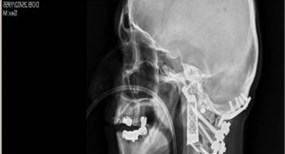

X-ray view

An X-ray view. Photo: ABC.net.au